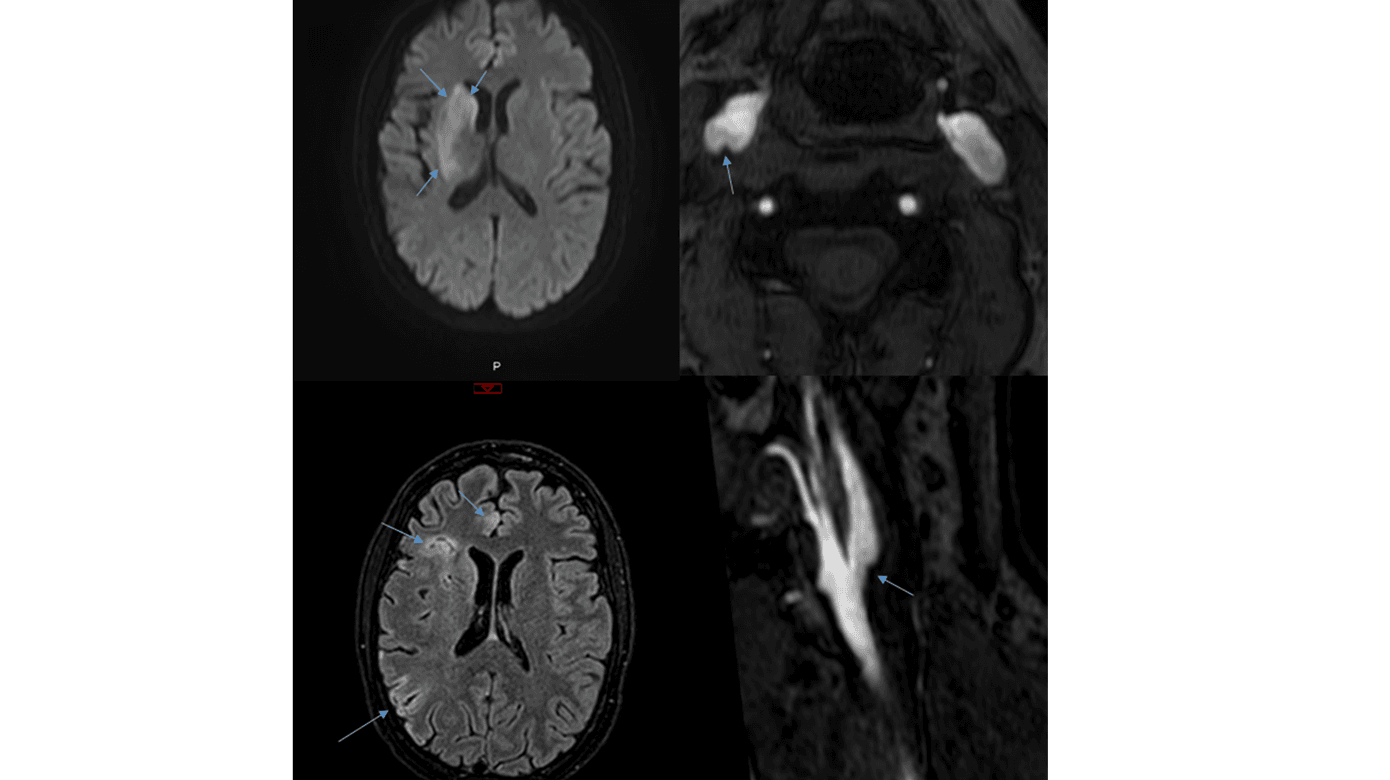

I løbet af den næste måned blev hun indlagt yderligere to gange med varierende venstresidige udfald, herunder central facialisparese, dysartri, visuel neglect, hemiparese og hemihypæstesi. Ved hver indlæggelse påvistes nytilkomne infarkter i det anteriore gebet i højre hemisfære (Figur 1 A + B).

Udredning med MR-skanning af cerebrum (MR-C) med kontrast, lumbalpunktur, helkrops-PET/CT for at udelukke underliggende malignitet og digital subtraktionsangiografi (DSA) kunne ikke forklare de gentagne iskæmiske strokes. Transøsofageal ekkokardiografi påviste et stort persisterende foramen ovale (PFO), og man påbegyndte behandling med dabigatran, idet nye infarkter var opstået trods DAPT. I den næste måned, i ventetiden på PFO-lukning, fik patienten et nyt infarkt i det anteriore gebet i højre hemisfære. Patientens PFO blev lukket, og hun overgik til behandling med clopidogrel. Elleve dage senere fik hun et nyt iskæmisk stroke med venstresidige udfald som tidligere beskrevet. MR-C inkl. angiografi påviste nytilkommen iskæmi i højre hemisfære med distal M1-trombe, og hun fik foretaget trombektomi.

Patienten havde altså nu haft seks iskæmiske strokes fra det anteriore gebet i højre hemisfære på trods af relevant pladehæmmerbehandling, antikoagulationsbehandling og vellykket PFO-lukning. På mistanke om CW udførtes MR-angiografi af halskar på ny, og denne gang rejste sig mistanke om karanomalien proksimalt i højre a. carotis interna (ICA) (Figur 1 C + D). Efterfølgende foretoges DSA forudgået af loading med tabletter clopidogrel og acetylsalicylsyre. DSA’en blev denne gang suppleret med skråoptagelser, som bekræftede fundet, der sås mest tydeligt i den sene kontrastfase [3] (Figur 1 E + F). Der blev anlagt en stent i CW i højre ICA, og patienten fortsatte i DAPT i vanlig vedligeholdelsesdosis.